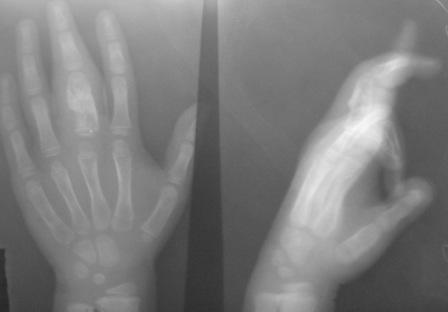

Уважаемые коллеги, на осмотре девочка 2006 г.рожд. Со слов матери 3мес. назад заметила припухлость основного фаланга 3-пальца, которая постепенно увеличилось до настоящего размера где-то в течении месяца, не болит, ребенка не беспокоит, признаки воспаления отсутствуют. Консультация онколога, биопсия - опухоль исключена (со слов матери), фтизиоортопед - тбс исключен. От основной фаланги 3 пальца к головке 4-пястной кости под кожей прощупывается хрящевидная ткань. Р-граммы от 10 декабря и 15 февраля, и фото прилагается. Что делать? Уважаемые коллеги, помогите! С уважением Абдурашид.

Добрый день, уважаемый Абдурашид. Судя по рентгенограмме, к сожалению не очень качественной, речь может идти о варианте дисхондроплазии, которую обозначают, как солитарную хондрому. Рентгенологически они проявляются в 3 вариантах-в виде интрамедуллярно и центрально расположенной энхондромы с вертеннобразным вздутием диафиза изнутри и истончением кортикальной пластинки, в виде опухоли, расположенной эксцентрично с заполнением части кортикального слоя и характерным костным козырьком, в виде экхондром, выступающих за пределы кости